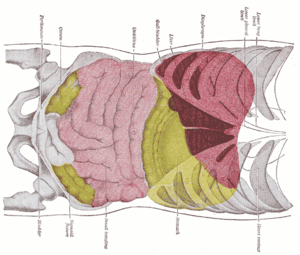

Interior of the cecum and lower end of ascending colon, showing colic valve Topography of thoracic and abdominal viscera

Topography of thoracic and abdominal viscera Endoscopic image of cecum with arrow pointing to ileocecal valve in foreground